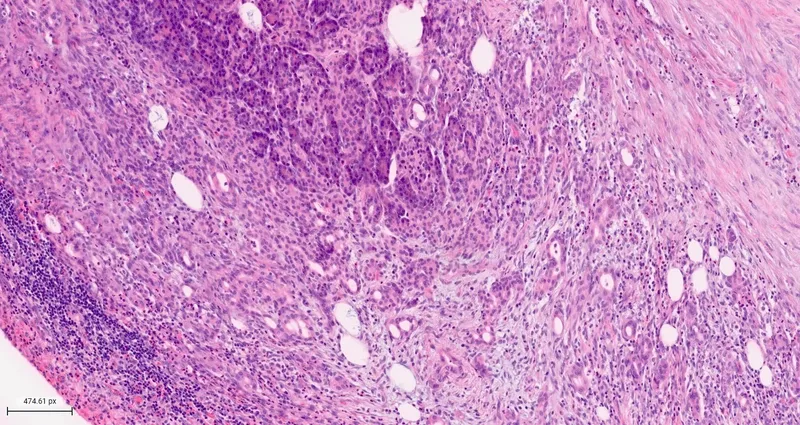

- Core Defect: Premature activation of trypsinogen to trypsin within acinar cells, instead of the duodenal lumen.

- Autodigestion: Activated trypsin triggers a cascade, activating other zymogens:

- Elastase → vascular damage & hemorrhage.

- Phospholipase A2 → membrane destruction & coagulative necrosis.

⭐ Trypsin is the key trigger. It not only digests pancreatic tissue but also activates the complement and kinin systems, amplifying inflammation and vascular permeability, leading to systemic complications.